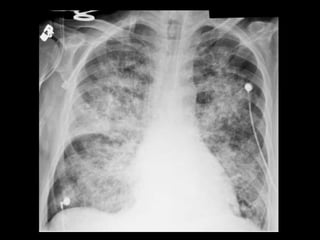

Êmbolo Séptico Embolia pulmonarséptica se apresenta com quadro insidioso de febre, tosse e opacidades pulmonares; Comumente visto em portadores de cateteres permanentes, endocardite da tricúspide, etilismo, infecções de pele e usuários de drogas IV; Manifestação radiográfica: opacidades nodulares bilaterais, com dimensões variadas que, em geral, apresentam escavações; A embolia séptica é com frequência complicada com empiema.

Êmbolo Séptico TC: modalidade importante para confirmar a presença de êmbolos sépticos quando a radiografia convencional de tórax permanece negativa; TC: nódulos bilaterais mais numerosos nas regiões periféricas dos pulmões e nas bases; Os nódulos podem ser bem circunscritos ou mal definidos e com frequência apresentam escavações; O sinal do vaso nutriz pode estar presente em 60- 70% dos casos.